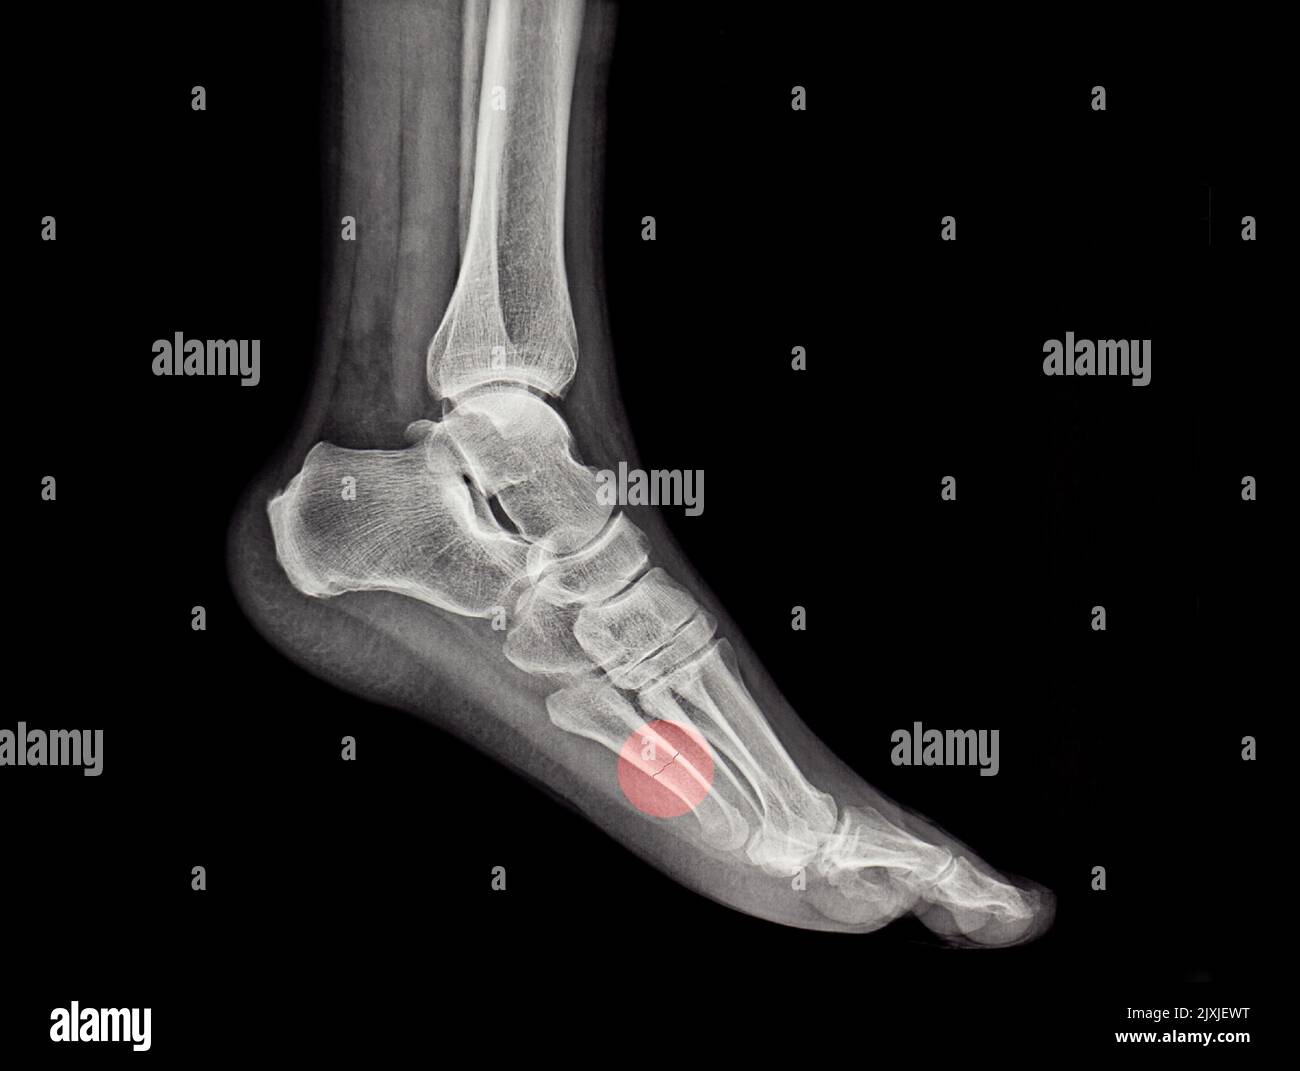

an xray of a human metatarsal bone fracture, diagnosis, broken Stock How To Tell If You Fractured Your Metatarsal metatarsal fractures may result either from direct or indirect violence, and they display a wide variety of injuries ranging from isolated, simple fractures. If you have a broken foot, you may experience throbbing pain that comes on suddenly or. you'll have pain and tenderness, especially when your weight is on your foot. what are the signs of. How To Tell If You Fractured Your Metatarsal.